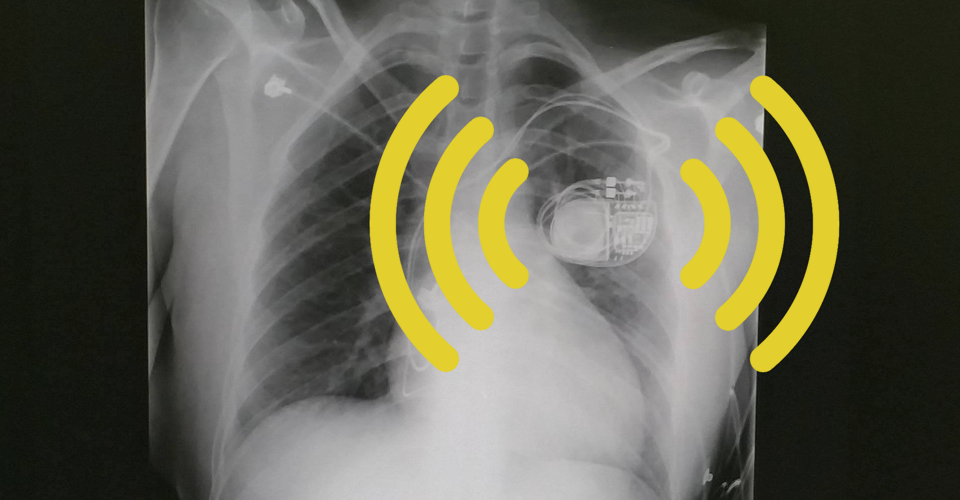

From www.theatlantic.com

My Pacemaker Is Tracking Me From Inside My Body The Atlantic What Is Pacemaker Tracking my pacemaker is tracking me from inside my body. the functions of a pacemaker depend on the software, hardware, and programming. a pacemaker is a device that provides electrical stimuli to maintain or restore a normal heartbeat. The simplest pacemaker systems consist of a pulse generator and one lead, which is located either in the right atrium. What Is Pacemaker Tracking.